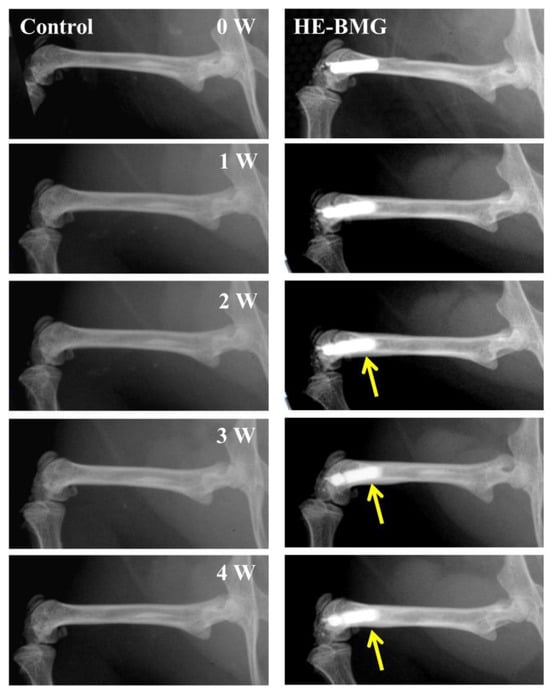

- Li, H.F.; Xie, X.H.; Zhao, K.; Wang, Y.B.; Zheng, Y.F.; Wang, W.H.; Qin, L. In vitro and in vivo studies on biodegradable CaMgZnSrYb high-entropy bulk metallic glass. Acta Biomater. 2013, 9, 8561–8573. [Google Scholar] [CrossRef] [PubMed]